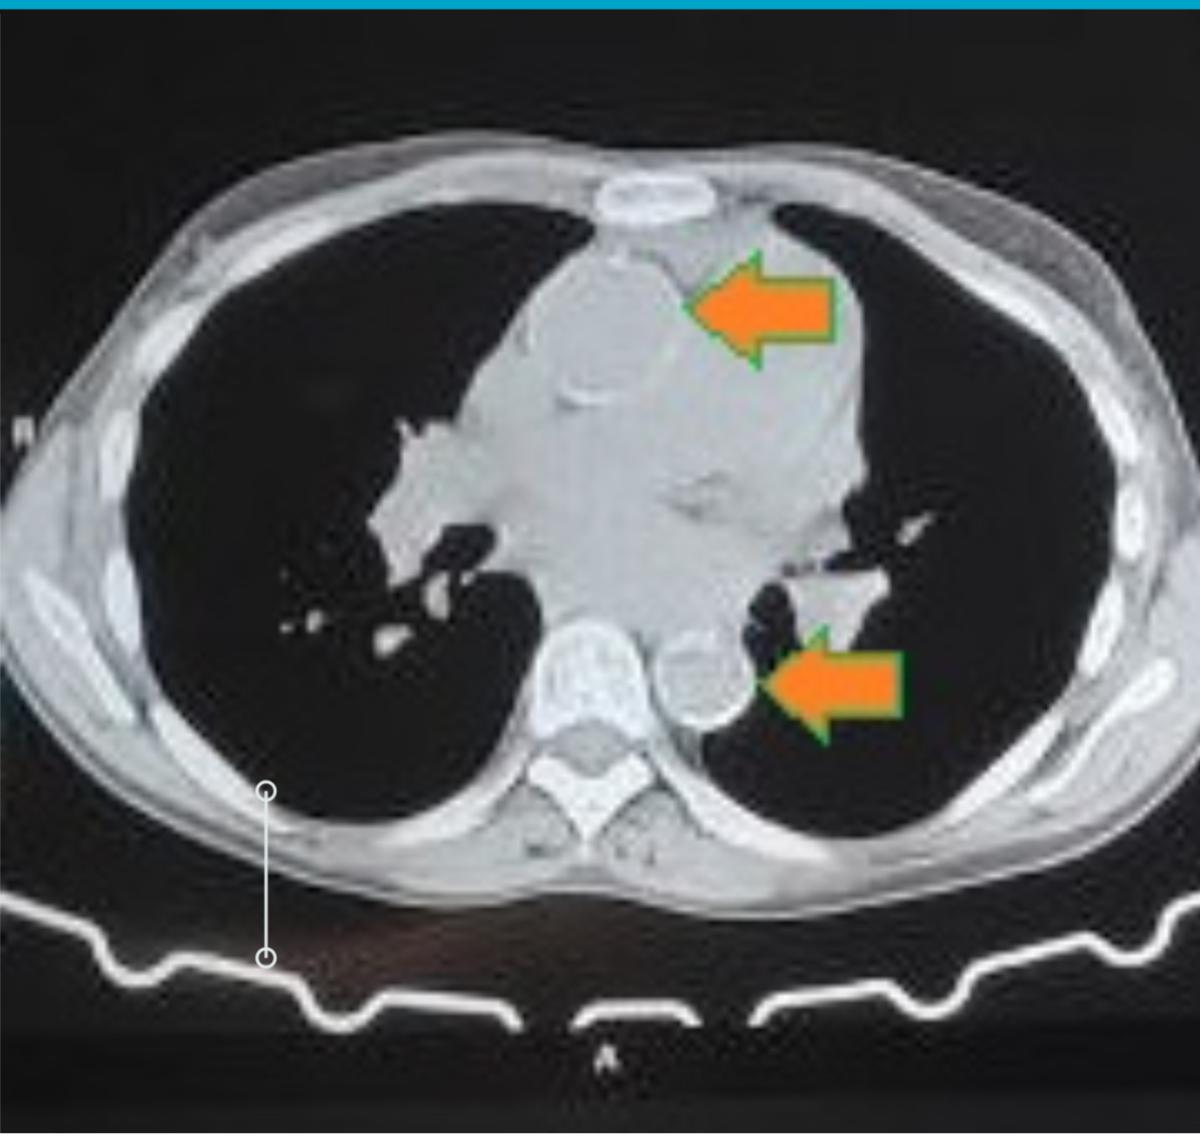

She had a history of hypertension and cachexia. The chest X-ray raised suspicion of aortic calcification, confirmed by a noncontrast CT scan, which demonstrated severe circumferential aortic calcification (porcelain aorta) with calcification-free femoral arteries (figures 1, 2).

Figure 2: CT showing the porcelain aorta.